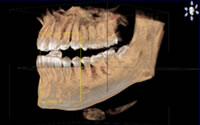

最新のCTレントゲンを導入しています。今まで見ることができない部分が立体的に、かつ詳細に確認できるので、正確な診断、緻密な治療計画の立案、安全で質の高い治療が可能です。

しかし、CTレントゲンは3D(立体的)での画像が得られ、従来の平面レントゲン画像に比べ、より豊富な情報を歯科医師に提供するレントゲンシステムです。

今まで見ることができない部分が立体的に、かつ詳細に確認できるので、正確な診断、緻密な治療計画の立案、安全で質の高い治療が可能です。

歯科治療の説明というのは、患者さんにとって分かりにくいものですが、ご自身の顎の状態を3D画像でご覧いただき、イメージもしやすいので『分かりやすい、安心する』という声を多数頂いています。